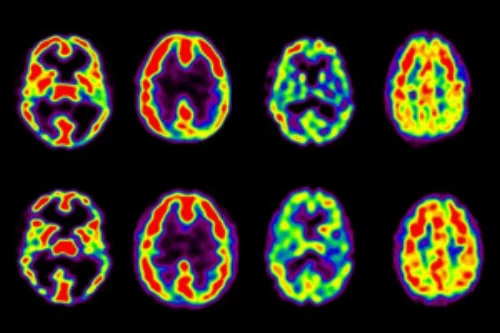

Different Types Of Meditation Change Different Areas Of The Brain, Study Finds

Now, a new study from the Max Planck Institute finds that three different types of meditation training are linked to changes in corresponding brain regions. The results, published in Science Advances, have a lot of relevance to schools, businesses and, of course, the general public.

The researchers wagered that training in each of these methods would lead to volume increases in corresponding brain areas. And this was largely what they found, as they scanned the participants’ brains at the end of each module and compared groups against one another. Training in Presence was linked to enhanced thickness in the anterior prefrontal cortex (PFC) and the anterior cingulate cortex (ACC), which are known to be strongly involved in attention. Affect training was linked to increased thickness in regions known to be involved in socially driven emotions like empathy; and Perspective training associated with changes in areas involved in understanding the mental states of others, and, interestingly, inhibiting the perspective of oneself.